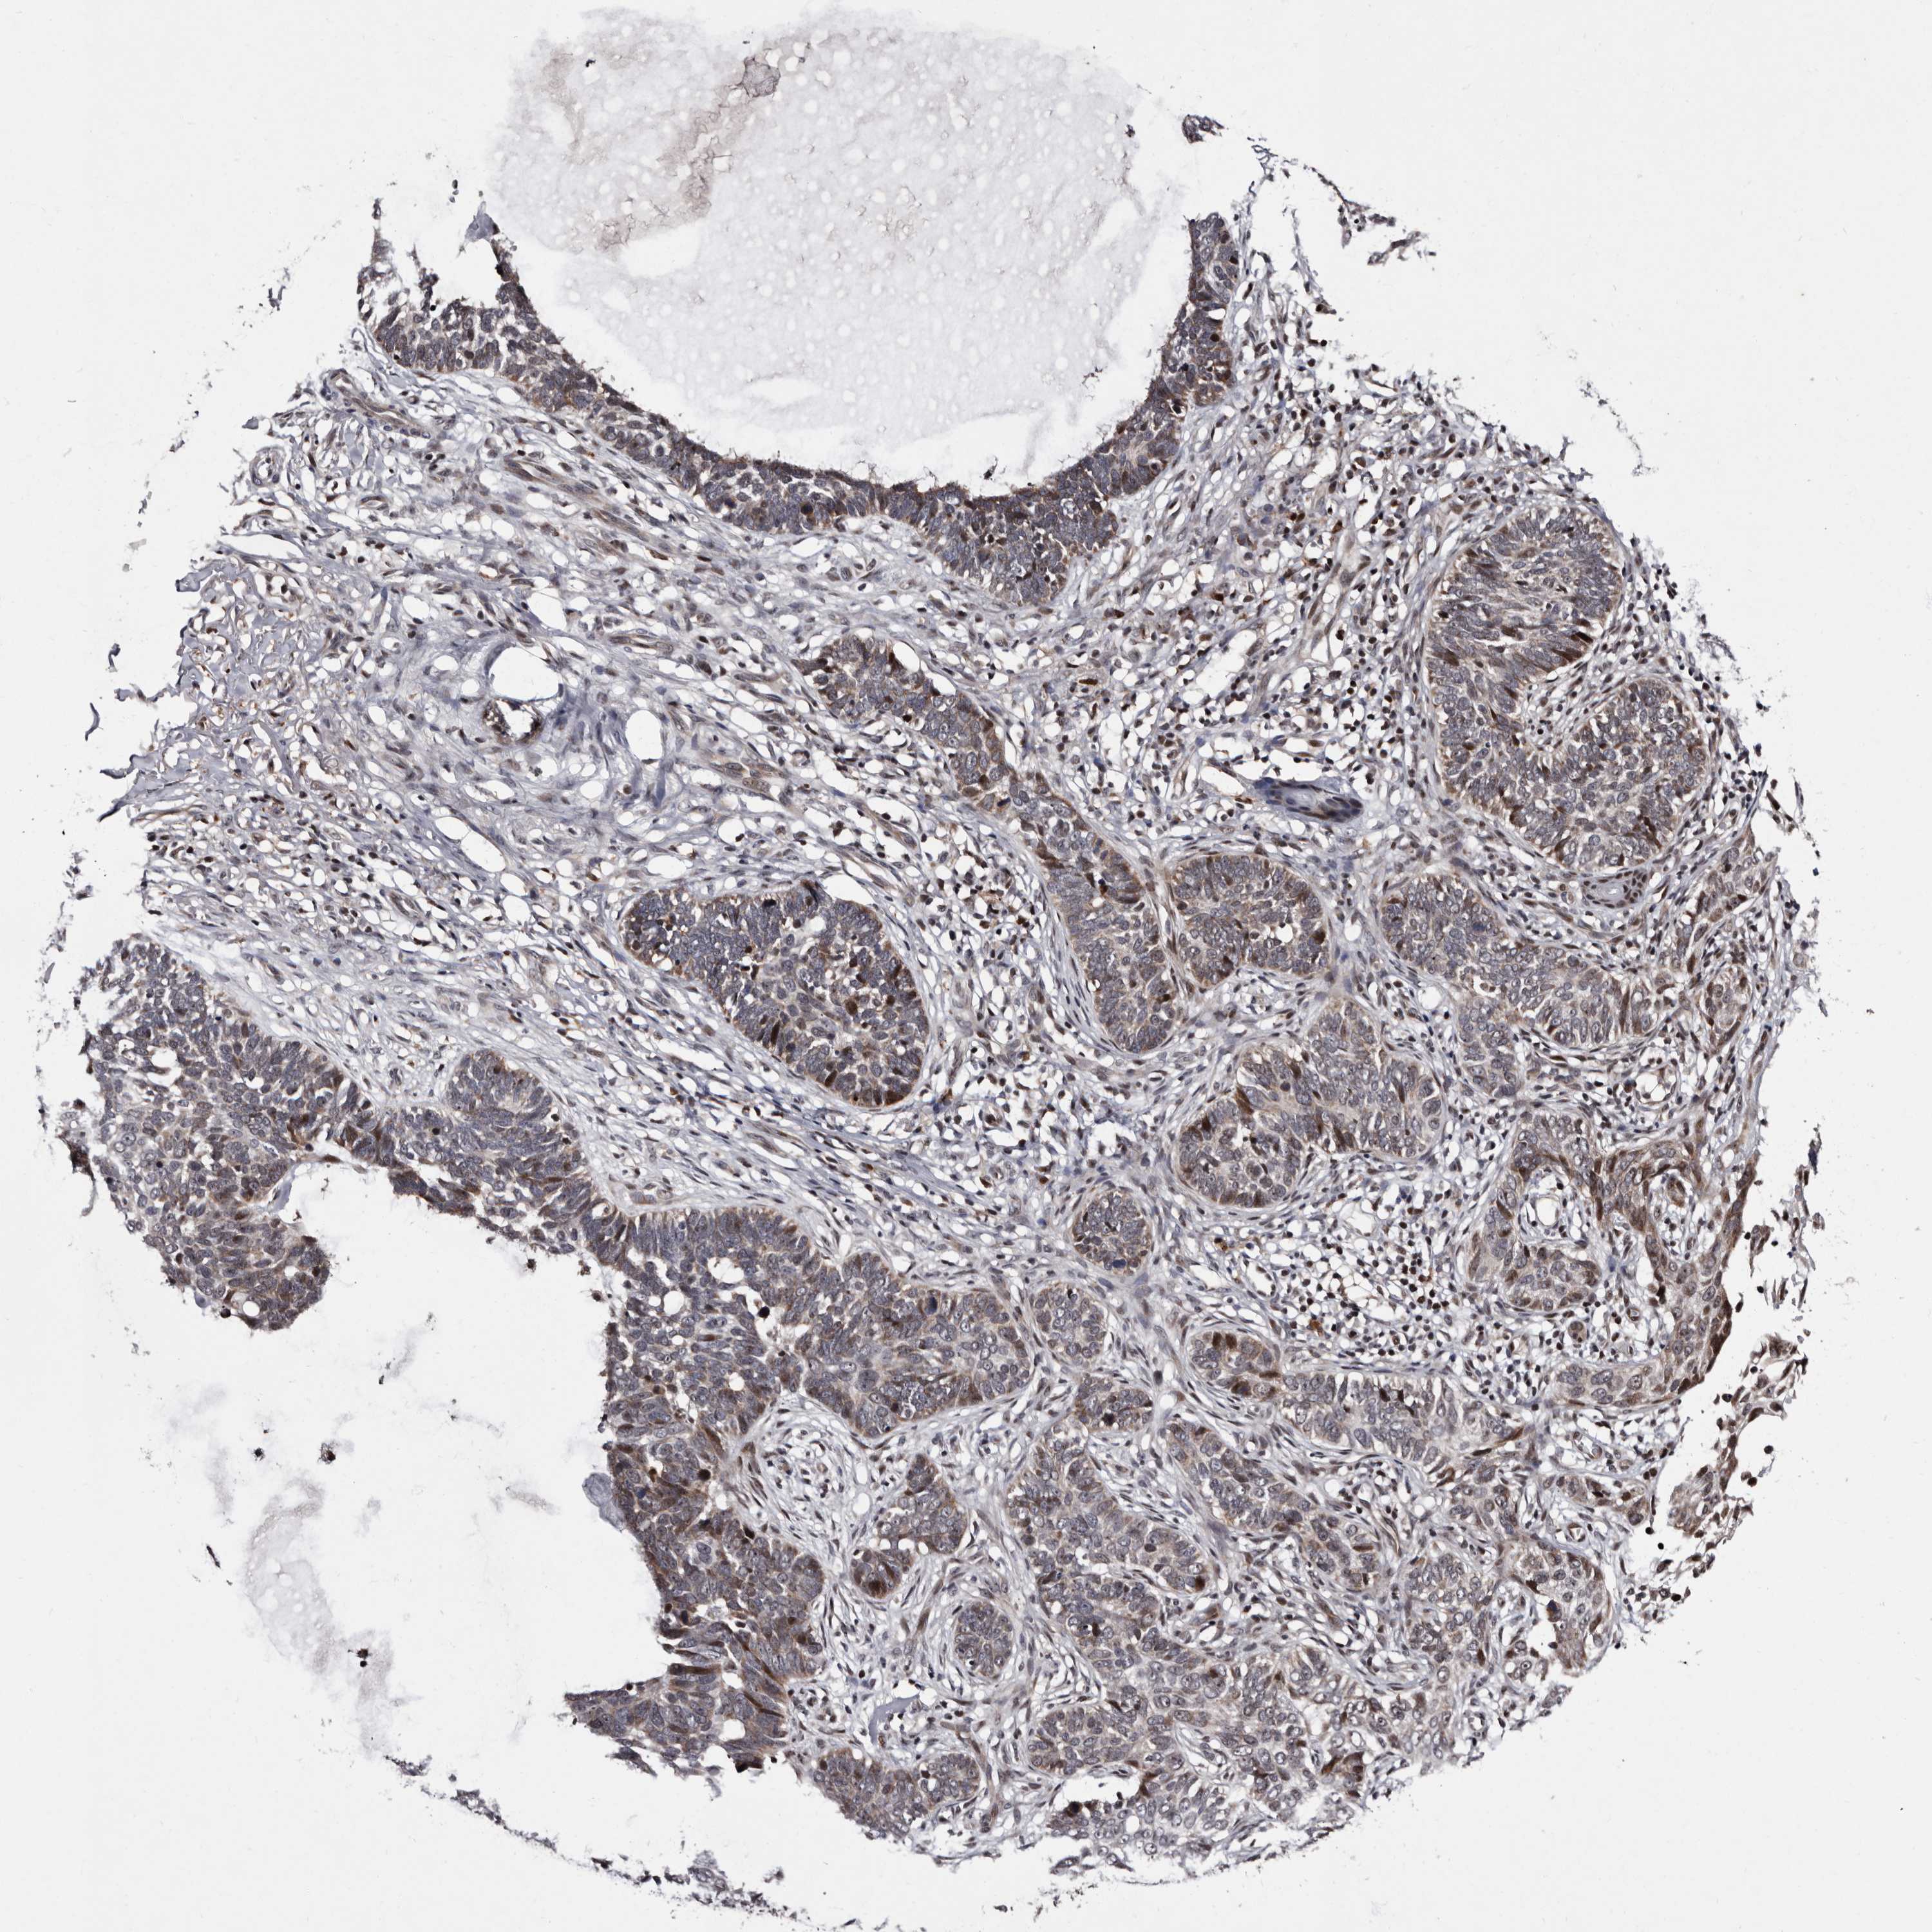

SKIN CANCER - Protein expressioni

A mouse-over function shows sample information and annotation data. Click on an image to view it in a full screen mode. Samples can be filtered based on level of antibody staining by selecting one or several of the following categories: high, medium, low and not detected. The assay and annotation is described here.

Each image is clickable and will lead to virtual microscopy that enables deeper exploration of all samples and also displays staining intensity scores, fraction scores and subcellular localization as well as patient and tissue information for each sample.

Antibody HPA025690

Staining

High

Intensity

Strong

Quantity

>75%

Location

Nuclear

Basal cell carcinoma